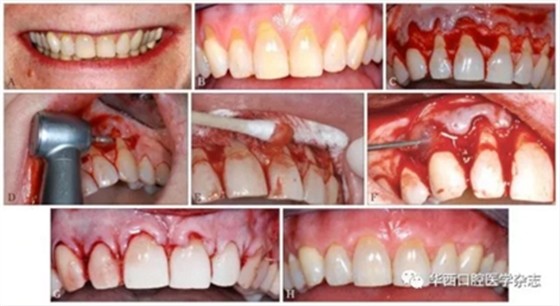

根据猪和人的釉质蛋白高度同源的特性,科学家们从小猪胚胎中提炼出EMD[15]。EMD不但能促进牙周膜成纤维细胞的生长,还可以抑制上皮细胞的生长。这是一个非常重要的特征,因为上皮的快速生长会与牙周膜和牙槽骨的生长产生竞争,在牙周组织再生过程中,如果上皮的生长占据了牙周膜和牙槽骨的再生空间,会造成牙周组织以修复结束,而没有形成真正的牙周组织再生重建。近年来,临床医生利用EMD再生牙周组织的特性,逐渐应用于根面覆盖手术[16]。研究[17]证实,利用EMD结合冠向复位瓣术治疗牙龈退缩,根面覆盖率与游离结缔组织结合冠向复位瓣术基本相同。EMD和冠向复位瓣术结合,不但较单做冠向复位瓣术牙根覆盖率高,而且明显增加了附着龈的宽度[18]。具体手术方法见图3。

A:患者中等高“微笑线”,但可见明显退缩的牙龈,影响美观;B:从左侧上颌尖牙到右侧上颌尖牙,牙龈广泛进行性退缩,根面敏感,临床附着水平和附着龈丧失;C:上颌从左侧尖牙到右侧尖牙翻起半厚瓣;D:常规根面处理,包括高速钻进行根面平整;E:pH为中性的24%乙二胺四乙酸处理根面;F:在缝合打结之前,将EDM注射在牙根表面上;G:无张力情况下,使用5-0可吸收线行连续褥式缝合,半厚瓣冠向复位将根面完全覆盖;H:术后8个月基本达到完全根面覆盖,而且角化组织(附着龈)增加了3~4 mm。

图 3 EDM结合冠向复位瓣手术